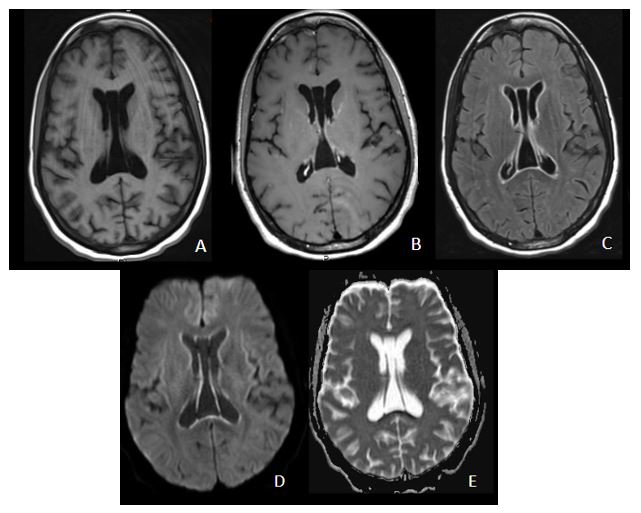

Secuencias en plano axial T1 sin contraste (A), T1 con contraste (B), FLAIR post-contraste (C), difusión (D) y ADC (E). Se aprecia, tras la administración de contraste, un realce ependimario generalizado, no nodular (A, B y C), que además muestra restricción a la difusión, con hiperintensidad en secuencia de difusión e hipointensidad en ADC (D y E)

Encefalitis por Citomegalovirus en paciente VIH.

Existen varias formas de presentación radiológica, tales como lesiones en sustancia blanca periventricular hiperintensas en T2 y FLAIR que pueden mostrar realce tras contraste, pequeño nódulos periependimarios que restringen en difusión o un realce ependimario, siendo especialmente característico éste último.